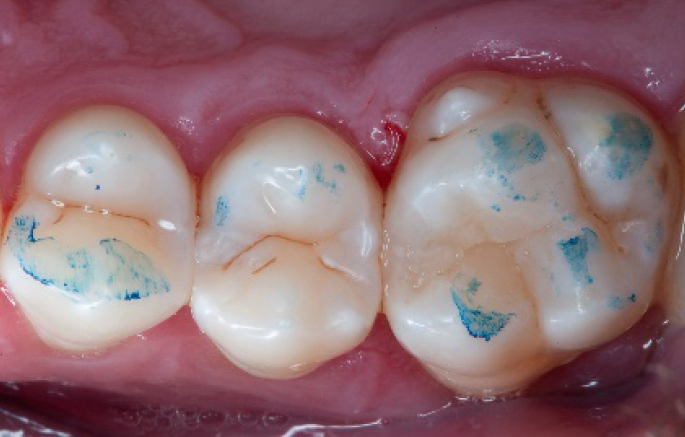

Initial situation of the patient

The patient came for a routine control appointment. She didn‘t report any symptoms but some bleeding during brushing.

Initial situation: an old class I composite restoration on 1.6. New caries on the mesial wall. Presence of plaque and inflammation.

Occlusal check